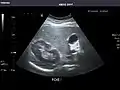

Spleen: Normal in size.

Spleen